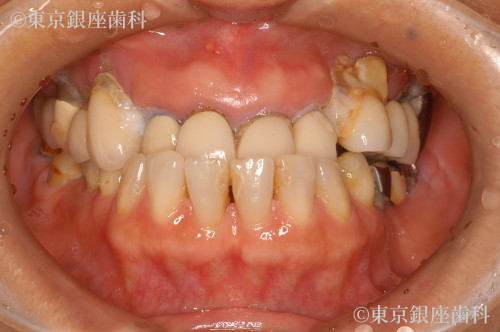

Before

After